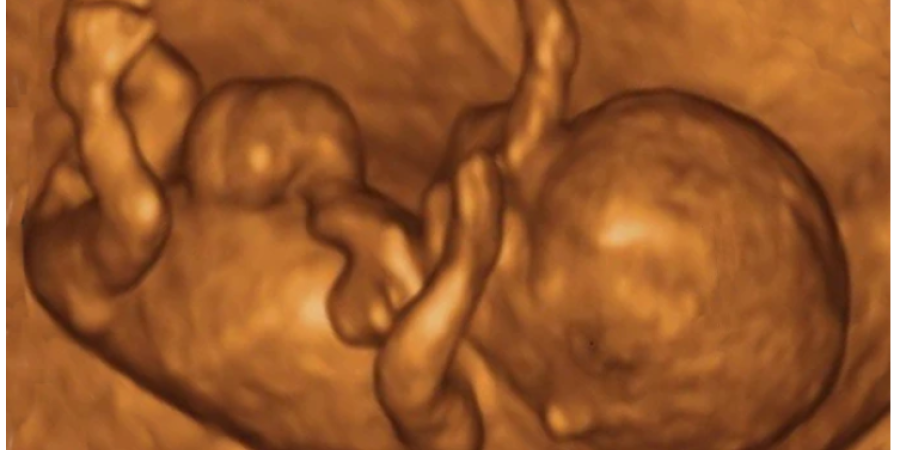

When a man's sperm fertilizes a woman's egg it creates a new cell known as the zygote. This is the first stage of human life and science has proven that human life in the form of a zygote has its very own DNA. Science shows that is what makes it distinct from both the mother's and father's own blueprint for individuality. It is a new human being.

Based on the instructions imprinted within the DNA blueprint, the new living person starts to develop its own arms, legs, nervous system, heart, and other necessary organs that will lead to its ability to sustain itself. Throughout this process it meets every criteria for the scientific definition of life: growing and reproducing cells, turning nutrients into energy through metabolism, responding to stimuli.